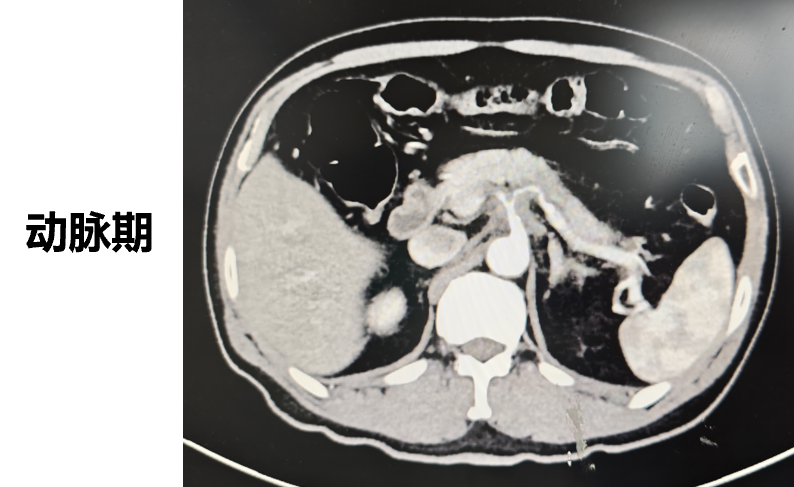

◈ 2022-7-19腹部MR增强扫描:提示T2WI及DWI胰腺体尾部信号稍高并胰管局限性稍扩张,肠系膜上动脉、腹腔干近段局部管壁增厚,需鉴别免疫相关性疾病累及或其他。

2022-7-19 上腹部MR增强扫描